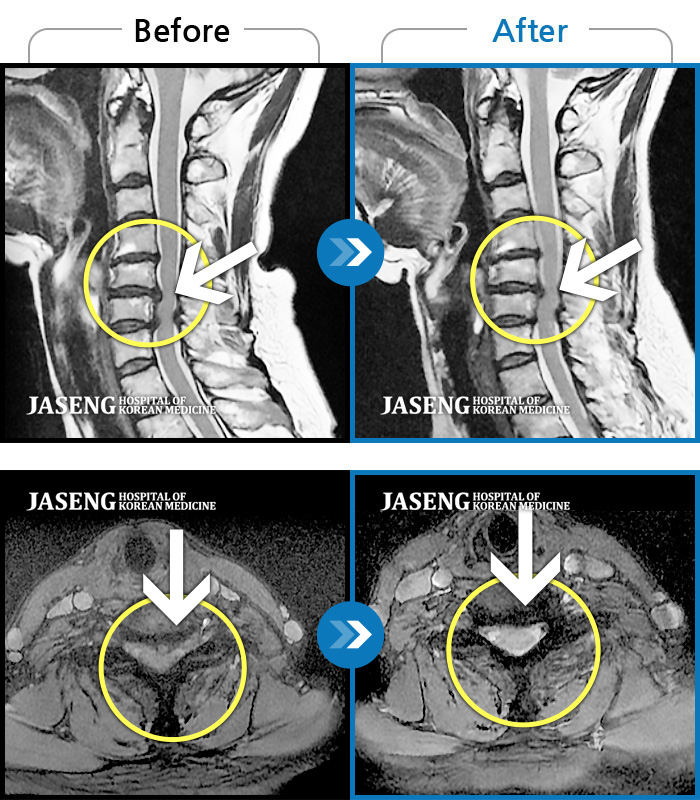

Before

After

목디스크로 후경부 좌측 통증, 좌측 손가락 저림

2018.01.15 ~ 2018.01.15